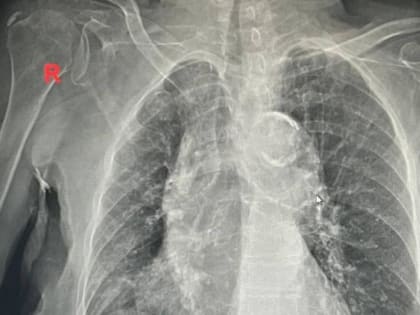

Пожилая женщина поступила в больницу с температурой около 40 градусов. Омский минздрав рассказал о том, как пульмонологи клинической больницы №1 имени Кабанова помогли 100-летней пациентке.

У бабушки обострился хронический бронхит.